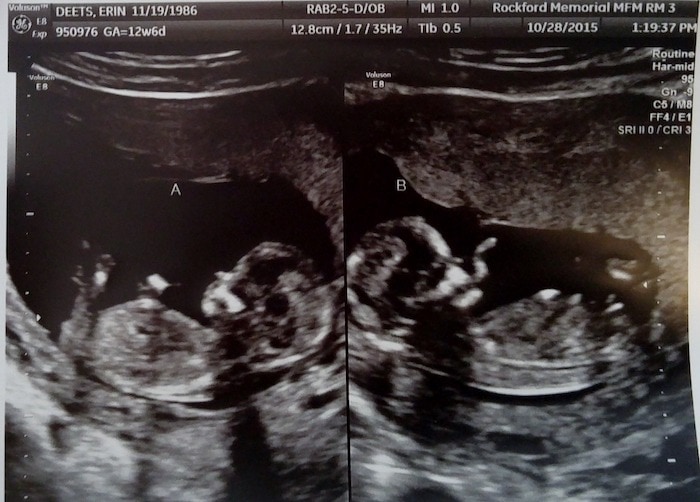

- Ultrasound Photos at 13 Weeks Pregnant With Twin

Ultrasound Photos at 13 Weeks Pregnant With Twin